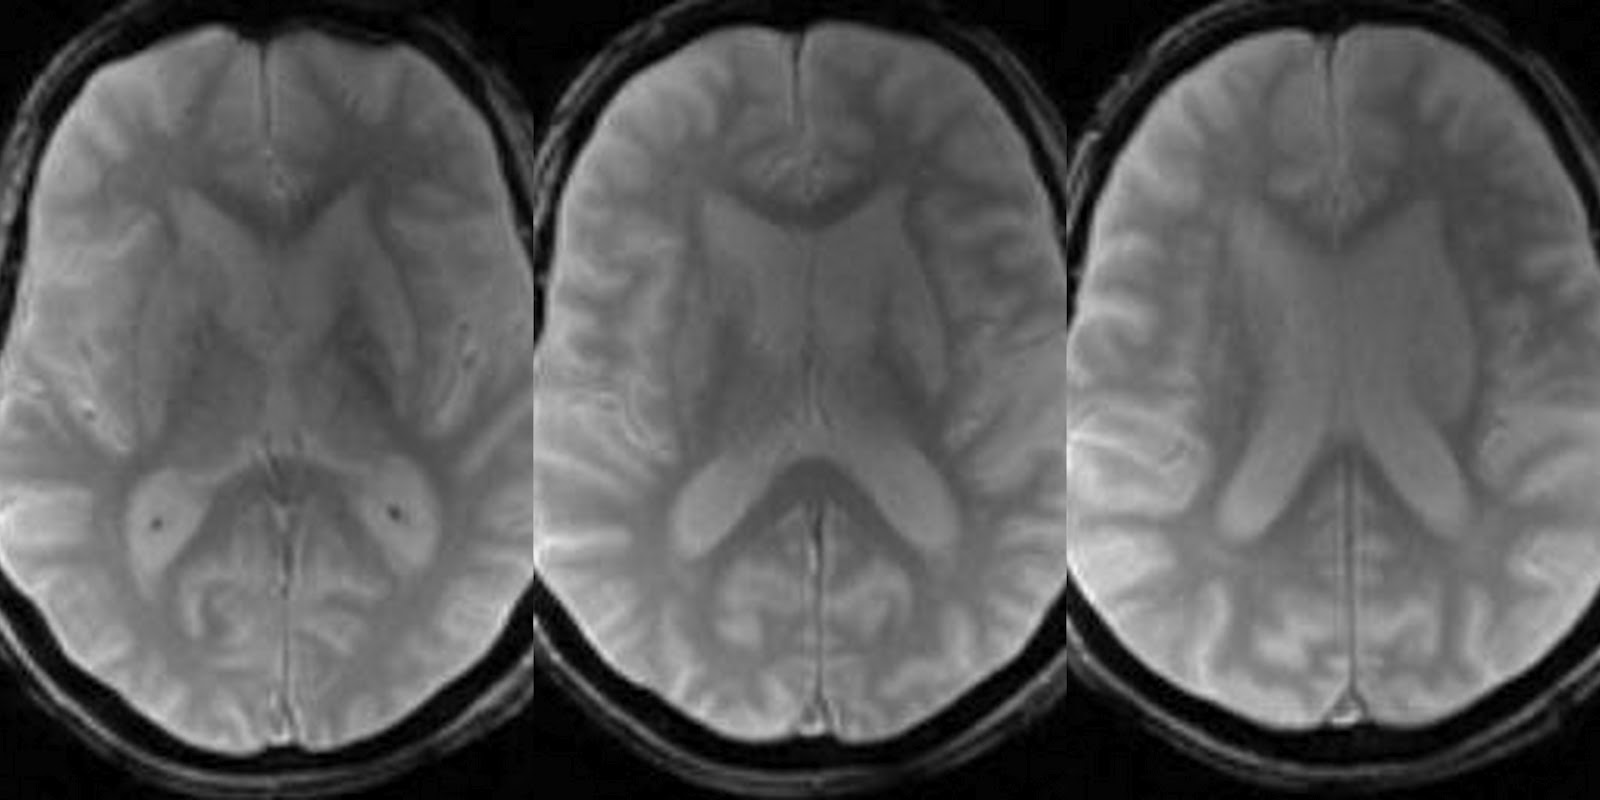

Bilateral hyperintensities of the basal ganglia in case 1 (A), 4 (B Basal Ganglia Hyperintensity Web the causes of basal ganglia t2 hyperintensity can be remembered using the mnemonic lint: Web t2 hyperintensity of the basal ganglia and thalami is generally present. Web the basal ganglia are highly metabolically active and are symmetrically affected in. Web mri reveals t2w and flair hyperintensity involves the basal ganglia, and hyperintense lesions of the hemispheric cerebral white. Web. Basal Ganglia Hyperintensity.